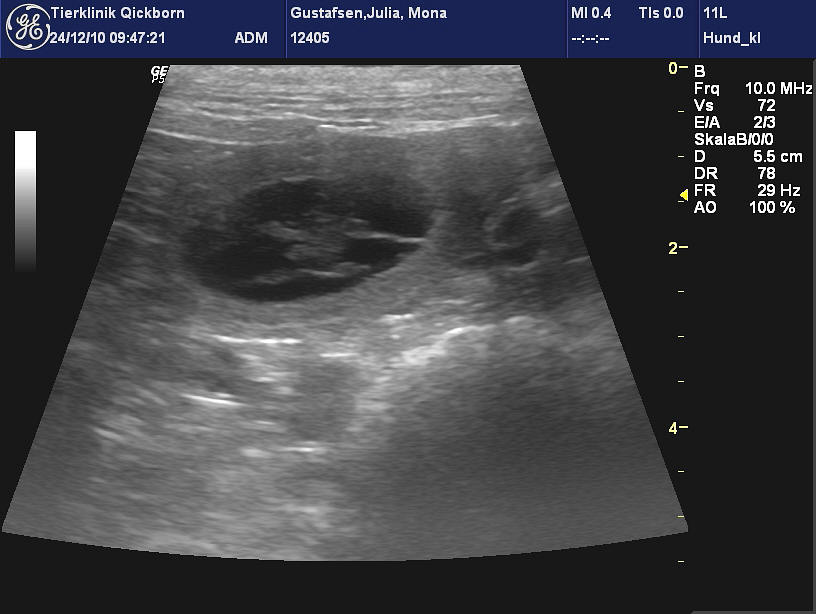

Pünklich zum Fest haben

wir kleine Herzen schlagen sehen....